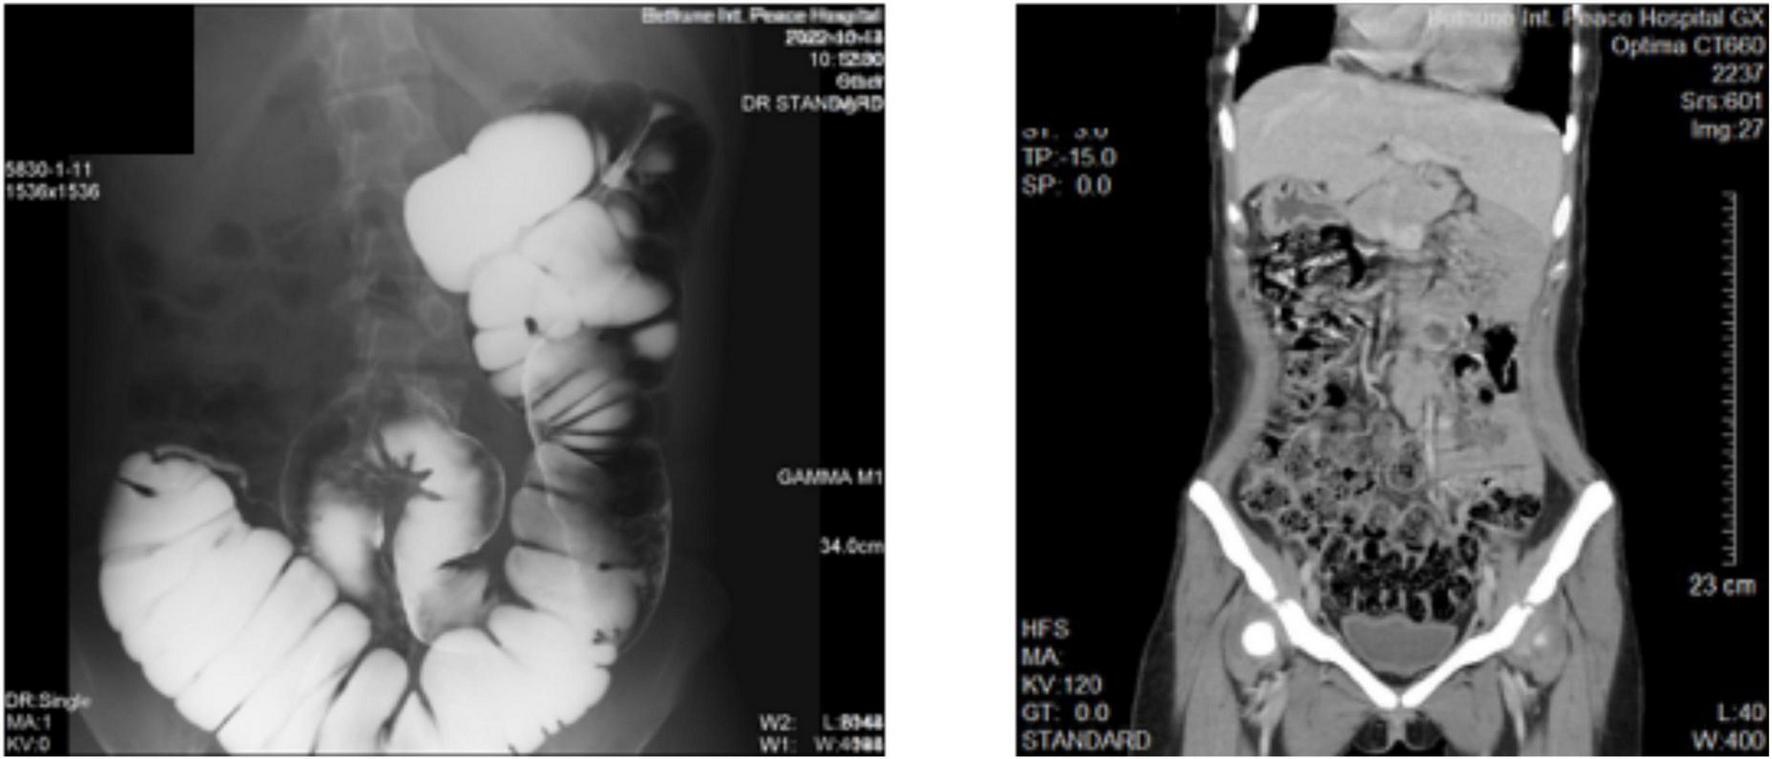

We now report a female patient, 20 years old, 44 Kg, with recurrent intermittent lower abdominal pain for more than 2 years, with exacerbation occurring 3 times, which improved significantly with interventions such as anti-inflammatory treatment when symptoms appeared. Half a month ago the symptoms reappeared and the patient was hospitalized for surgical treatment (Figure 1).

Figure 1. Imaging images of the patient’s abdomen. (Left) Barium examination. (Right) Full abdominal CT scan.